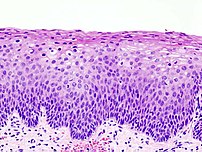

The earliest microscopic change corresponding to CIN is epithelial dysplasia, or surface lining, of the cervix, which is essentially undetectable by the woman. The majority of these changes occur at the squamocolumnar junction, or transformation zone, an area of unstable cervical epithelium that is prone to abnormal changes.[12] Cellular changes associated with HPV infection, such as koilocytes, are also commonly seen in CIN. While infection with HPV is needed for development of CIN, most women with HPV infection do not develop high-grade intraepithelial lesions or cancer. HPV is not alone enough causative.[13]

It most commonly occurs at the squamocolumnar junction of the cervix, a transitional area between the squamous epithelium of the vagina and the columnar epithelium of the endocervix.[12] It can also occur in vaginal walls and vulvar epithelium.

_normal_squamous_epithelium.jpg)

Historically, abnormal changes of cervical epithelial cells were described as mild, moderate, or severe epithelial dysplasia. In 1988 the National Cancer Institute developed "The Bethesda System for Reporting Cervical/Vaginal Cytologic Diagnoses".[15] This system provides a uniform way to describe abnormal epithelial cells and determine specimen quality, thus providing clear guidance for clinical management. These abnormalities were classified as squamous or glandular and then further classified by the stage of dysplasia: atypical cells, mild, moderate, severe, and carcinoma.[16]